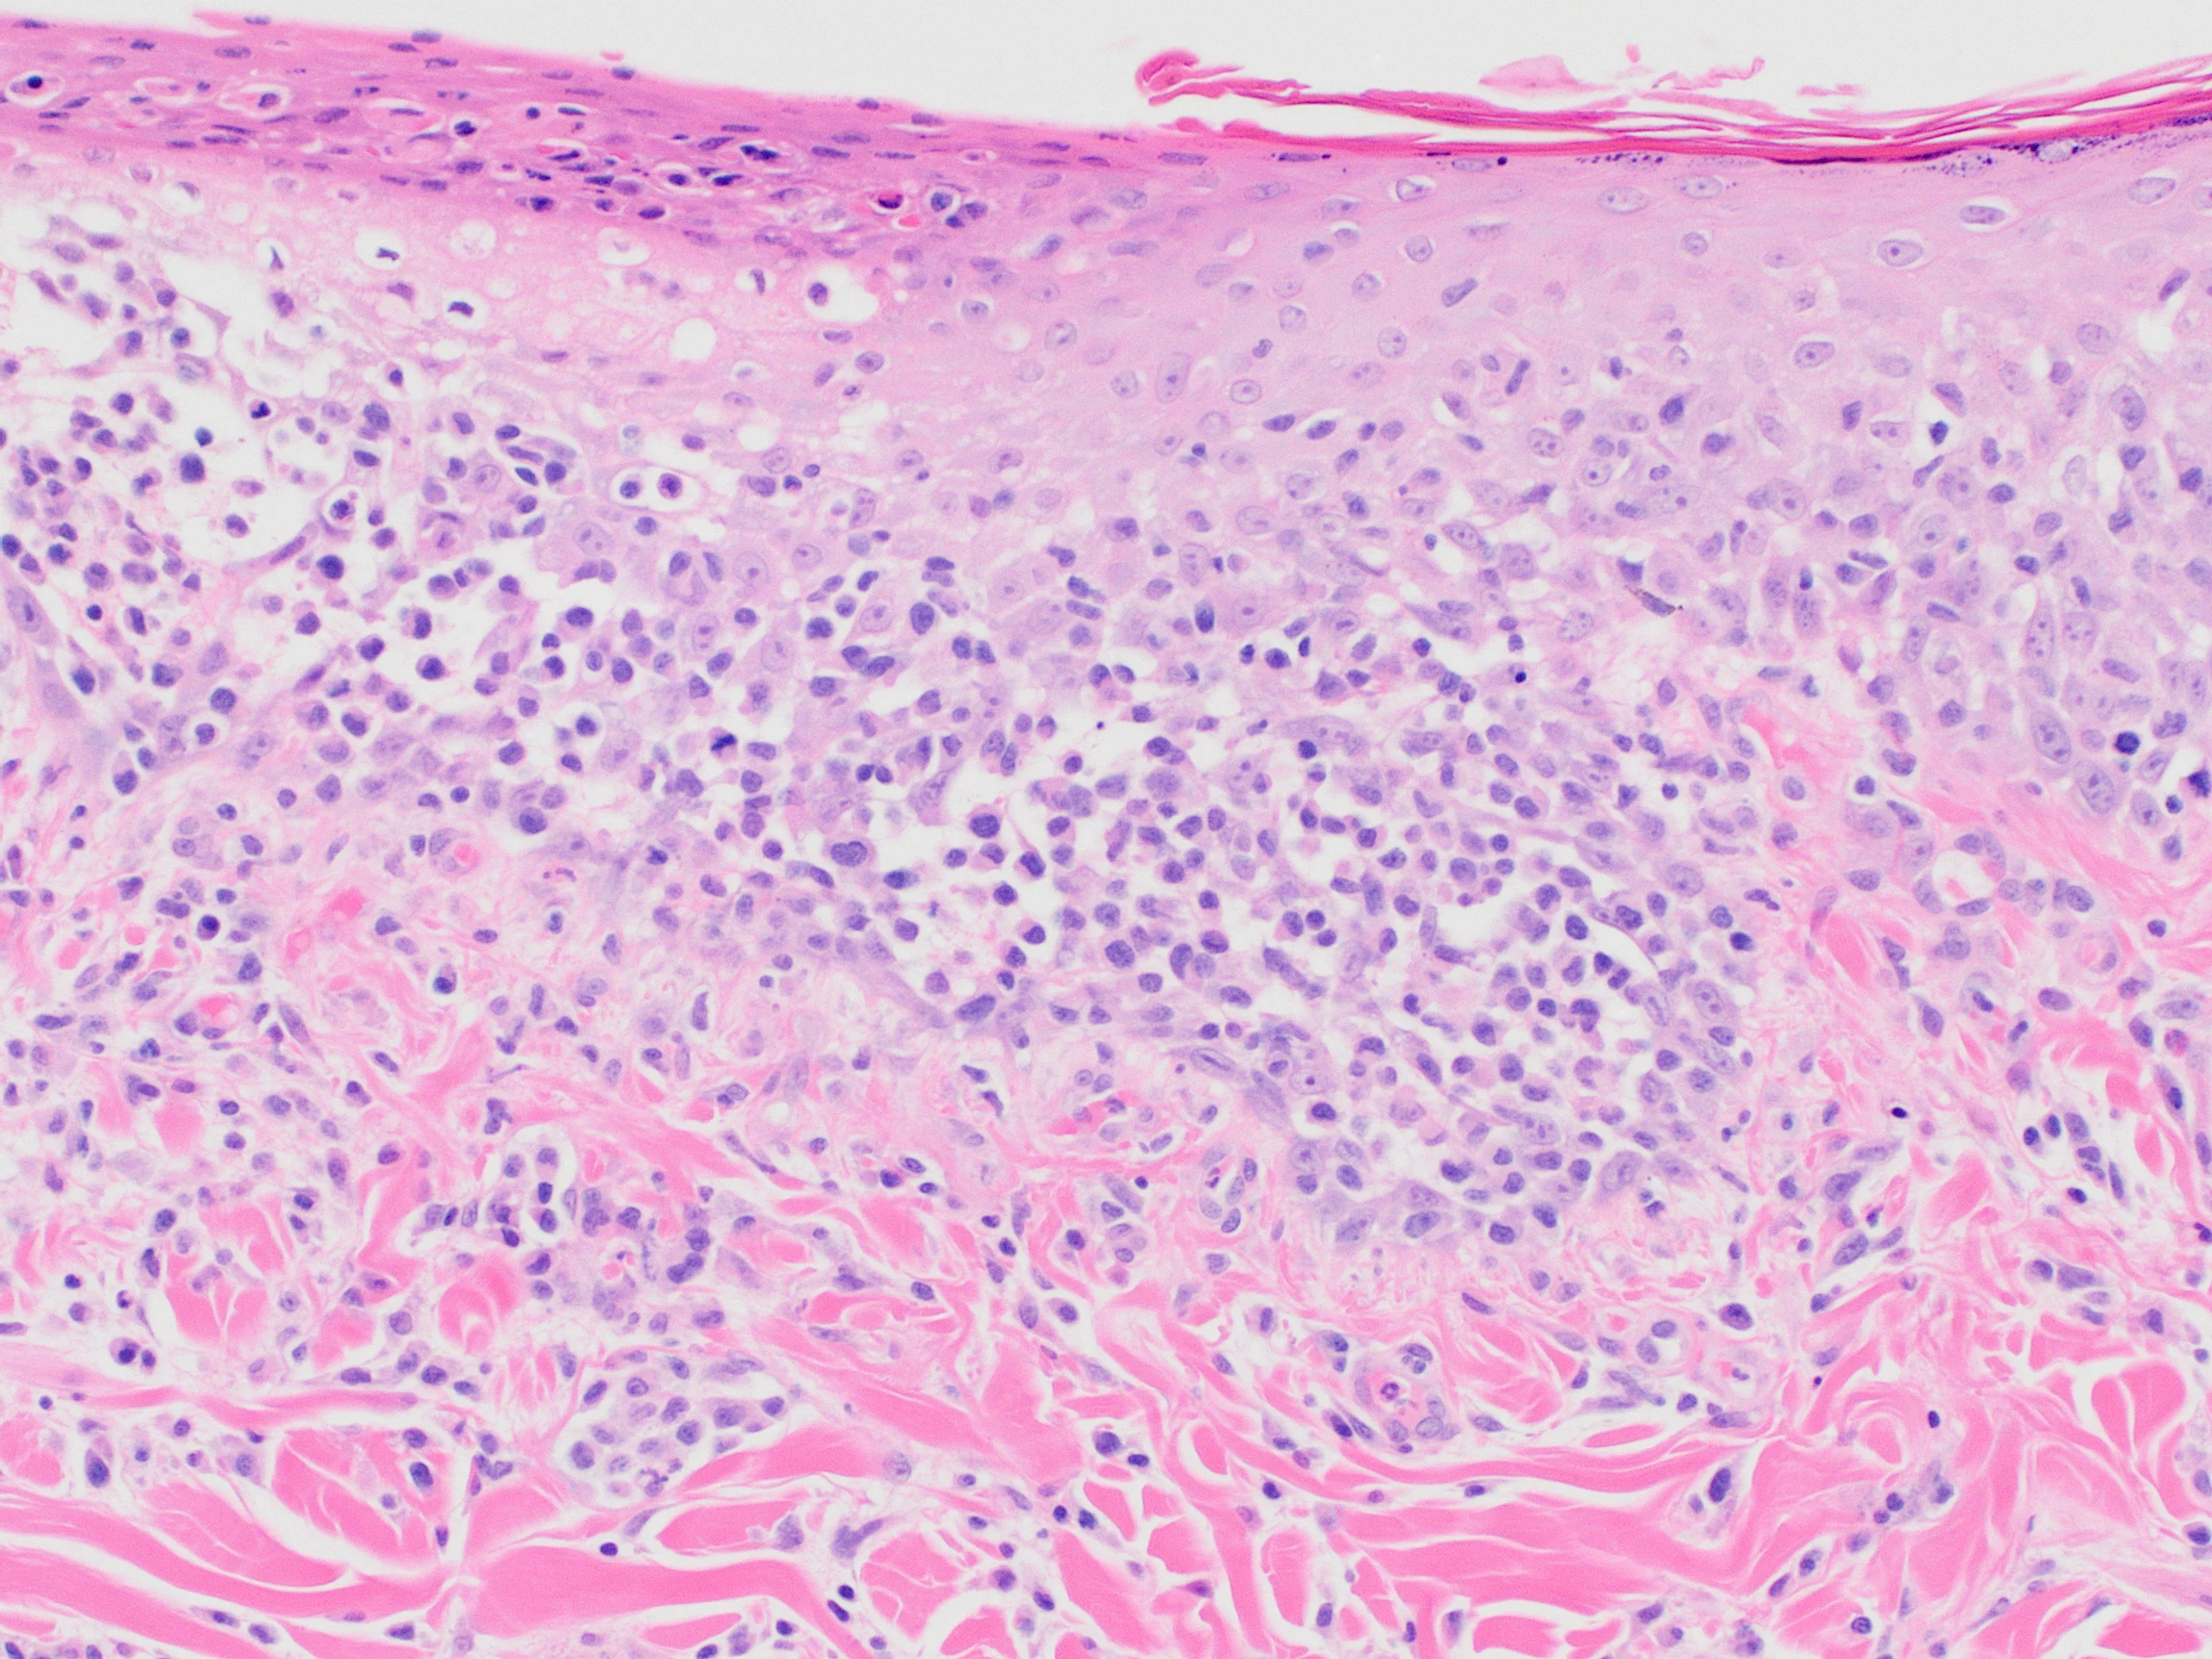

Histopathology showed round cells in the dermis, subcutis, follicular epithelia, apocrine glands, and epidermis (Figure 3) that occasionally formed small intraepidermal nests (ie, Pautrier's microabscesses, which are enlarged, atypical T-lymphocytes forming aggregates or found diffusely within the epidermis). Neoplastic round cells had distinct cell margins and central nuclei with finely stippled, normochromatic chromatin and 1 to 2 small nucleoli. Mitoses ranged from 3 to 16 per high-power field (40×), with 64 mitotic figures counted in 10 randomly selected high-power fields.

Histopathology showing infiltration of the epidermis by neoplastic lymphocytes. Image courtesy of Dr. Shannon Martinson